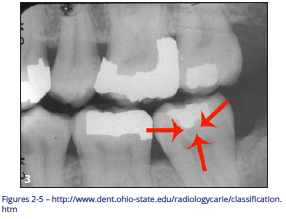

Pit and Fissure Caries (Figure 2)

Includes Class I occlusal surfaces of posterior teeth, lingual pits of maxillary incisors, buccal surfaces of mandibular molars.

Figure 2